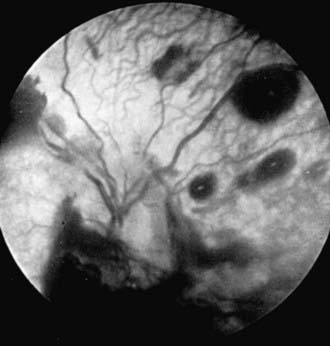

Child abuse (Chapter 37) is a major cause of injuries to the eye and orbital region. The possibility of nonaccidental trauma must be considered in any child with ecchymosis or laceration of the lids, hemorrhage in or about the eye, cataract or dislocated lens, retinal detachment, or fracture of the orbit. Inflicted childhood neurotrauma (shaken baby syndrome) occurs secondary to violent, nonaccidental, repetitive, unrestrained acceleration-deceleration head and neck movements, with or without blunt head trauma, in children typically <3 yr of age. Inflicted childhood neurotrauma accounts for approximately 10% of all cases of child abuse and carries a mortality rate of up to 25%. Detection of abuse is not only important in order to treat the pathology that is discovered but also to prevent further abuse or even death. The ocular manifestations are numerous and can have a prominent role in recognition of this syndrome. Retinal hemorrhage is the most common ophthalmic finding and occurs at all levels of the retina. The pattern of hemorrhage helps to distinguish this disorder from other causes of retinal hemorrhage or from accidental injuries (Fig. 627-3). Retinal hemorrhages can occur without associated intracranial pathology.

image

Figure 627-3 Retinal hemorrhages in an abused child with subdural hematoma.